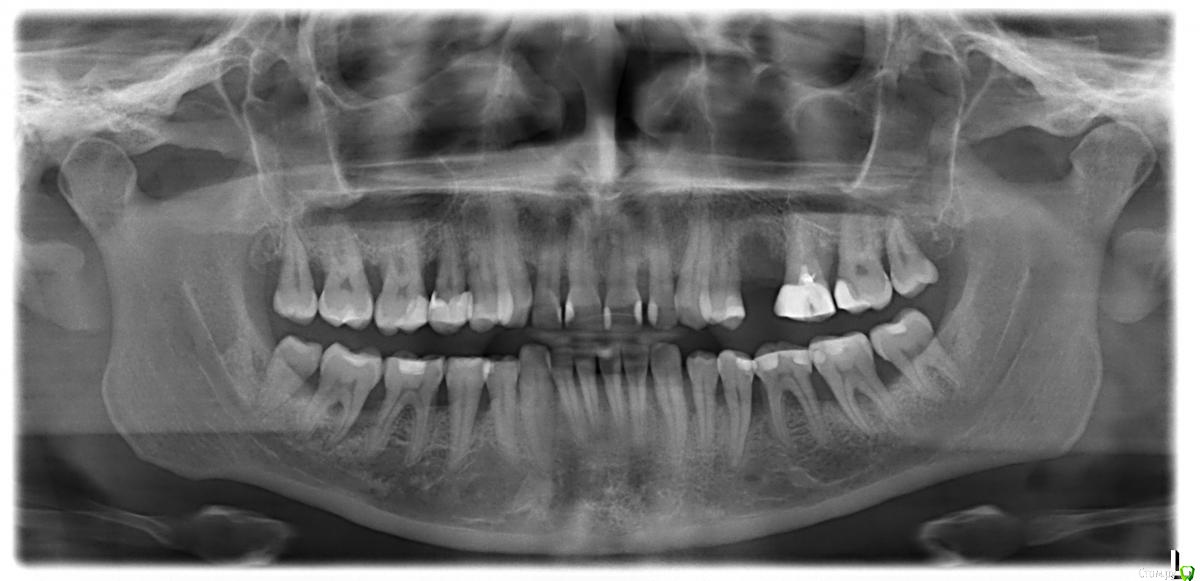

31n Опубликовано 26 октября, 2019 Поделиться Опубликовано 26 октября, 2019 (изменено) Добрый день! См. снимок ОПТГ от 29 апр 2019 г.Исходные данные: наследственных заболеваний нет, анализы (общий/биохимия, гормоны) в норме (Т4 своб чуть завышен - 0,835), ничего не болит/не беспокоит, 36-37 малоподвижны, состояние ротовой полости "ничего такого, прилично" (местами рецессия десны).Пока собираю консенсус-мнение о плане лечения.Предложенные планы:1. Клиника по ОМС: собрать анализы, заболевание "инактивно" (на зондирование в области 47 болевой реакции нет), показан вектор и плазмолифтинг.2. Частная клиника:этап I - собрать анализы, пройти курс антибиотиков перед лечением (обнаружен? гной), показан: закрытый кюретаж (карманы 5-7 мм), вектор, гидроорошение, закладка лекарств;*что смущает: как достоверно подтвердить необходимость приёма антибиотиков?+ Насколько целесообразен закрытый кюретаж при таких карманах и, как следствие, весь этап I в целом.этап II - открытый кюретаж (либо лоскутная операция) с остеопластикой (будет видно после 1-го этапа). Буду очень признателен Вам за изложение личного мнения (плана лечения). Изменено 26 октября, 2019 пользователем 31n Ссылка на комментарий

Bier Опубликовано 4 ноября, 2019 Поделиться Опубликовано 4 ноября, 2019 толкового пародонтолога в Москве могу посоветовать. В личку напишите, если нужно. Дорого. Мое мнение вы уже процитировали. Я бы пока предложил удалить зубы мудрости и далее по протоколу.А/б терапия, закрытый кюретаж, открытый кюретаж выборочно.Окклюзионную схему можно проверить парралельно. Ссылка на комментарий